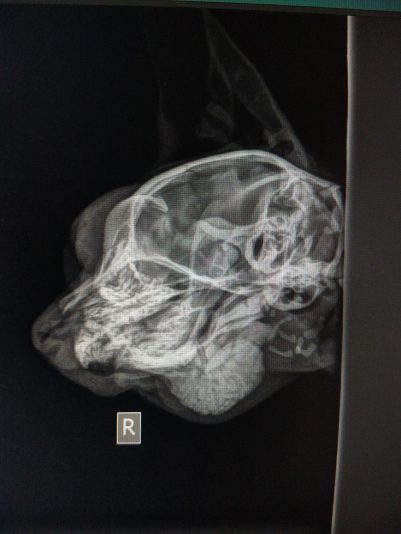

Vermoeden pituitary dwarfism - IGF1 normaal

Signalement: Kattin intact van 7m, Europese Korthaar

Anamnese: Enkele weken geleden reeds klachten van manken op achterpoot en gezwollen tarsus. Was de kleinste van het nest en groeide moeilijk. Sinds verhuis erg stil en zit veel minder leven in. Eten, drinken, urineren en defeceren nog normaal.

Klinisch onderzoek: rustig maar alert. HF…